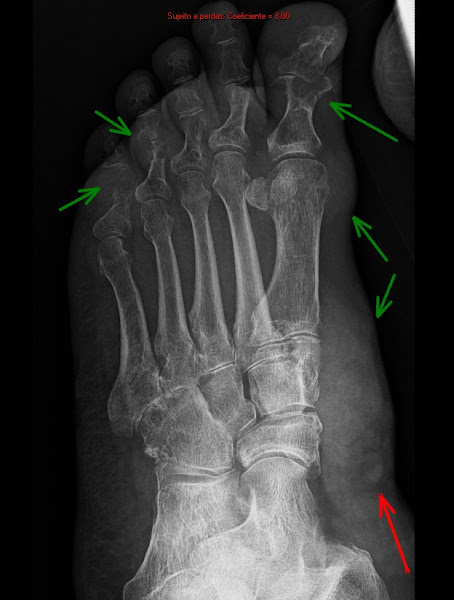

Radiological cases of daily practice including magnetic resonance imaging (MRI), computed tomography (CT), positron emission tomography (PET/CT) and X-Rays, without wasting time in your routine. Click on READ MORE button to enlarge images and click on the SUBSCRIBE button to receive e-mail updates. Thank you.